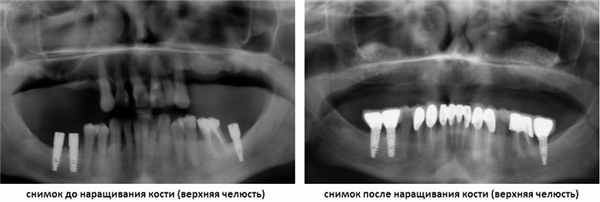

Современные методики подсадки и пластики костной ткани создают условия для протезирования и имплантации зубов при имеющейся атрофии костной ткани